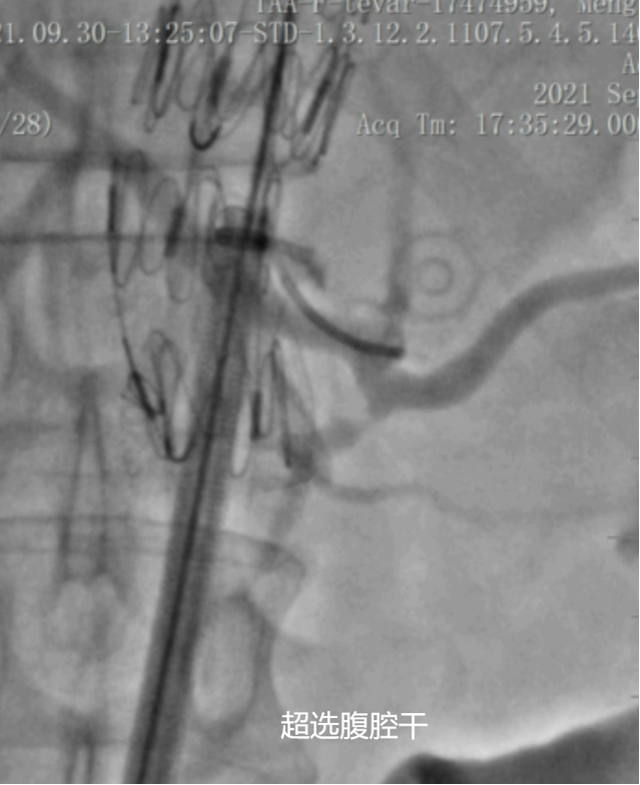

分支超选对位

① 术中定位

实时造影,显示屏标记

Roadmap技术

CT图像融合技术

② 高处释放:

导丝导管长鞘选中目标分支之后下拉支架

下面支架未完全释放,有空间超选;

导丝可以先出窗口后,灵活超选分支血管;

开窗位置靠下或者主动脉较细时,下拉困难;

在目标位置释放大支架,直接超选目标分支

窗口对位准确后,导丝可以从窗口直接进分支,导管长鞘跟进容易;

没有下拉不动的风险;

大支架初期调整到位后,无需多次调整。